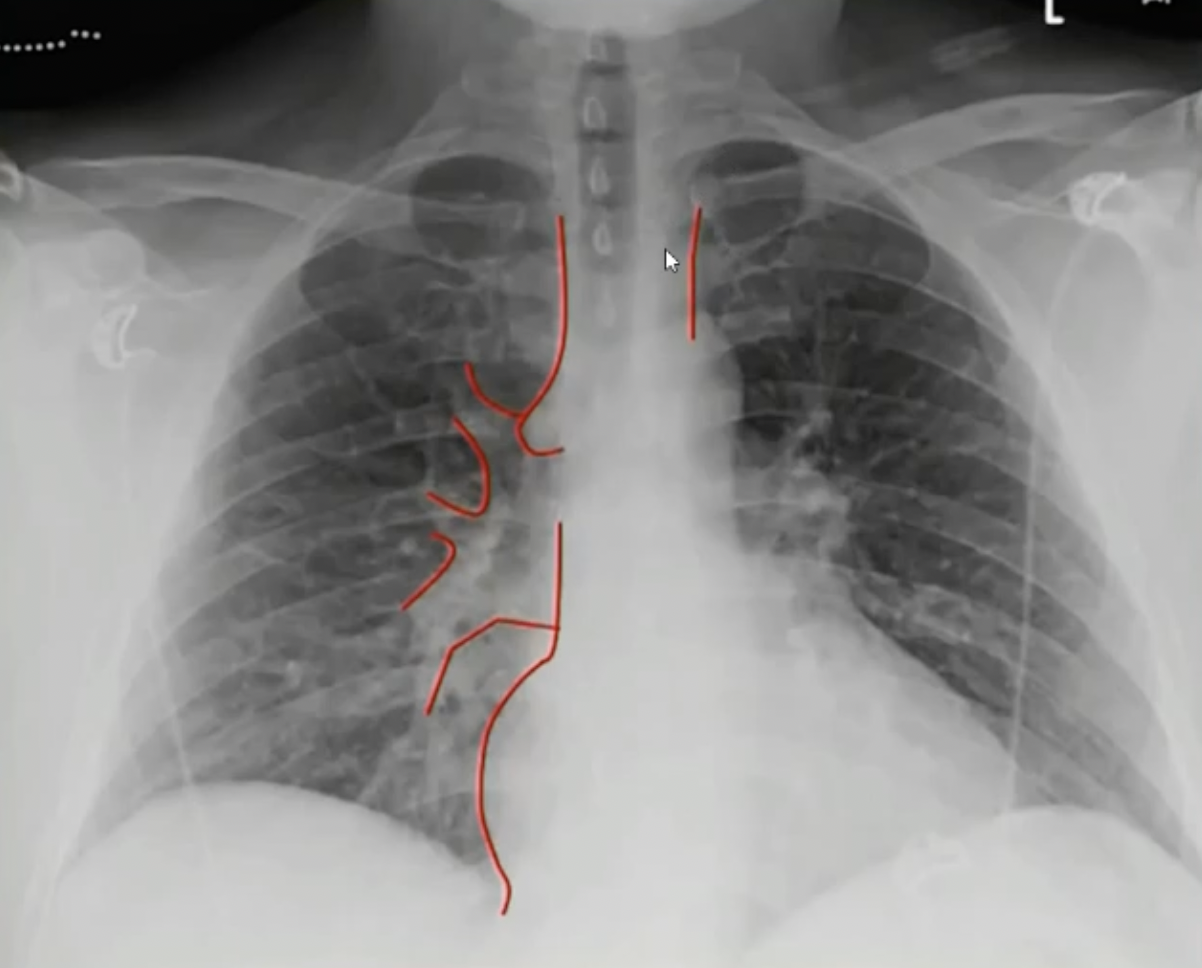

# 正位